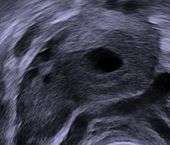

Human ovary with fully developed corpus luteum

- Corpus Luteum cyst: hemorrhage into persistent corpus luteum. Commonly regresses spontaneously.